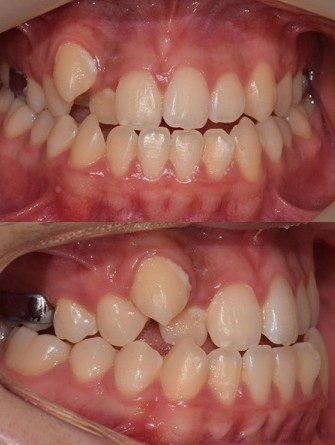

[4일차 모습 (2022.01.29)]

장치를 돌리고 4일차 사진입니다.

대문니 사이가 벌어지기 시작합니다.

역시 나이가 어려서 반응이 빨리 오네요.

벌어짐도 확인했고, 구정 땐 쉬고 이어서 계속 돌리기 시작했습니다.

[2주차 모습 (2022.02.05)]

돌리기 시작한 지 2주 차 사진입니다.

대문니 싸이가 2미리 이상 벌어졌네요.

입안을 살펴볼게요.

지속적인 양치질 잔소리로 양치질이 많이 좋아졌습니다.

그리고 어금니를 보시면 처음과는 다르게 윗니가 아랫니를 덮는 양상을 보이고 있습니다.

앞니를 보면 아직 약간 부족하지만 윗니가 아랫니보다 조금 덮으려는 양상을 보이고 있습니다.

장치 하나로 정말 큰 변화를 보이고 있습니다.